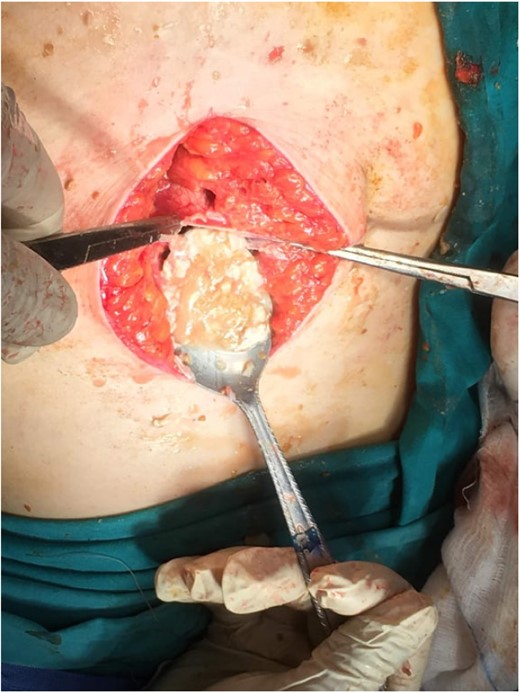

Subsequently, surgical exploration was performed. A preperitoneal sizable cyst was revealed, which developed in the abdominal wall without the involvement of any abdominal viscera or wall peritoneum. The macroscopic appearance of its content suggested that the mass was indeed a hydatid cyst (Figs 4 and 5). Incision upon the cyst wall and evacuation of its content were performed, without spilling of the content. Hypertonic solution of sodium chloride (NaCl 15%) was then injected in the remaining cavity, followed by the placement of a Pezzer catheter.

Total cyst drainage without spillage. Subsequent Pezzer tube placement through incision site.